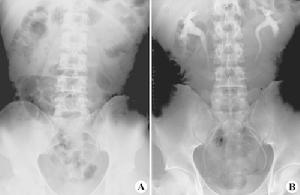

正常腹X線平片(A)和靜脈腎盂造影片(B)由於醫學設備的發展,磁共振成像(MRI)技術也可以使用2D、3D-TOF等特殊技術,利用泌尿系統內的尿液來實現只針對水的成像,無需逆行插管或是靜脈注射造影劑,就可真正實現無痛檢查。

靜脈腎盂造影靜脈腎盂造影(IVP):又稱排泄性尿路造影。系由靜脈注入含碘造影劑,造影劑主要通過腎臟排泄,經過腎小球過濾、腎小管濃縮後,自腎集合管排出後兒顯影。含有造影劑的尿自腎盞排到腎盂、輸尿管及膀胱時均可顯影。成人在注射造影劑後,壓迫輸尿管,在第7、15、30分鐘各拍片1張。兒童應減少照相次數,除平片外,於注藥後第3~5分鐘,拍腎臟照片1張,第7~12分鐘拍第2張,包括腎臟、輸尿管和膀胱。